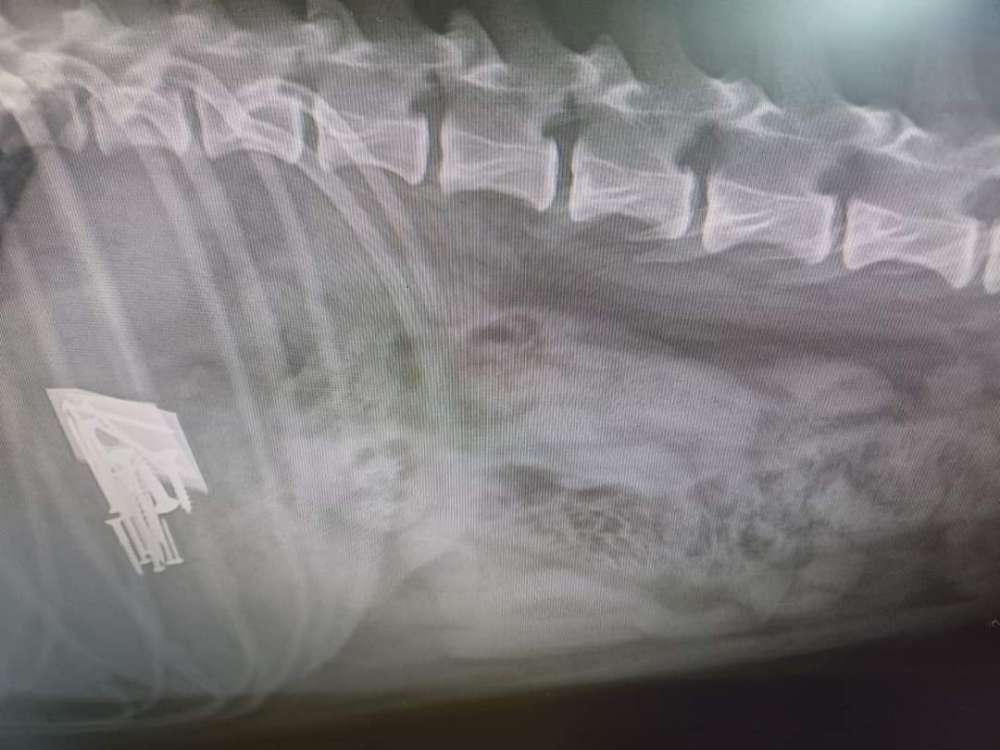

‼️‼️Köder mit Cuter-Messer und Nägeln gespickt ‼️‼️

Im Raum Pressig, Landkreis Kronach

Quelle/Text/Bild: FB; Tierklinik Lautertal